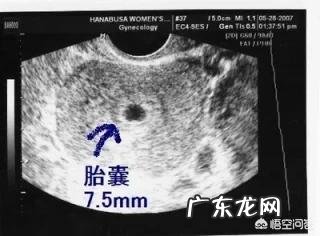

怀孕60天,孕囊发育大小是怎样的?我来说下5-9周每周孕囊大小 。

【怀孕60天,孕囊发育大小是怎样的呢?】接下来说说每周孕囊发育的情况 。

首先教大家一个公式,怀孕7周前的孕囊直径大小㎝=孕周-4 。比如你现在怀孕5周,那么孕囊大小为1厘米 。

孕囊的发育因人而异,有的人孕5周去照B超可能见不到,因为太小了,孕囊小有可能跟排卵延迟着床延迟有关 。

但按照大多数人来看的话,孕5周一般能看到孕囊了,大小约为0.5-1.5厘米 。